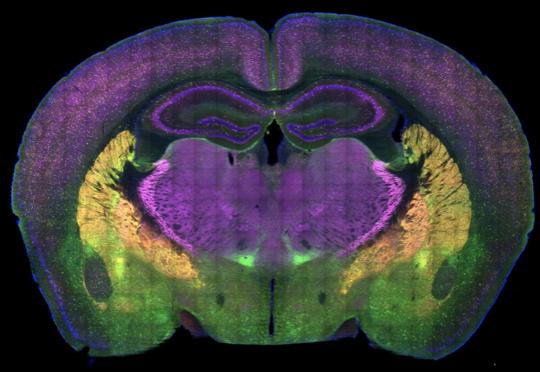

小鼠大脑的横截面图,不同颜色表示影响动物作出正常社交和社交回避选择的脑区。

神经科学家Damon Page博士等采用了多种创新技术来应对这一挑战。他们在小鼠身上发现了两种能够独立控制社会偏好的特殊神经通路。两者都将前额叶皮层的高级思维和决策区域与大脑的情绪调节中心杏仁核相连。

研究小组发现了连接小鼠边缘下皮质和基底外侧杏仁核的一个神经通路。如果该通路受到抑制,则会损害动物的社交行为。另一个关键通路连接了大脑前皮质和基底外侧杏仁核。

论文作者Aya Zucca表示,该通路的激活也产生了类似的对社交行为的损害。小鼠和人类都使用相应的大脑区域来处理社会信息,因此小鼠模型是研究这些问题的理想模型。